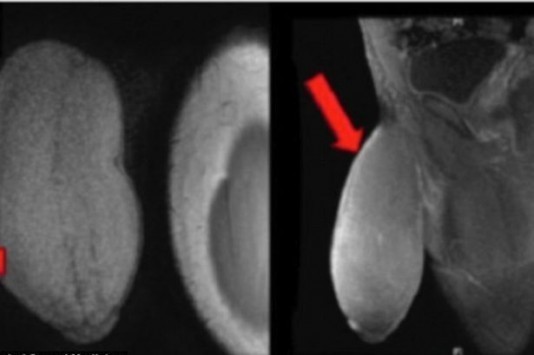

Ο έφηβος αναγκάστηκε να περάσει την πόρτα του χειρουργείου, καθώς το πέος του έχει αφύσικο μέγεθος. Όπως ισχυρίζονται οι γιατροί, το πάχος του είναι ίδιο με μίας μπάλας του ράγκμπι ή ένα γκρέιπφρουτ!